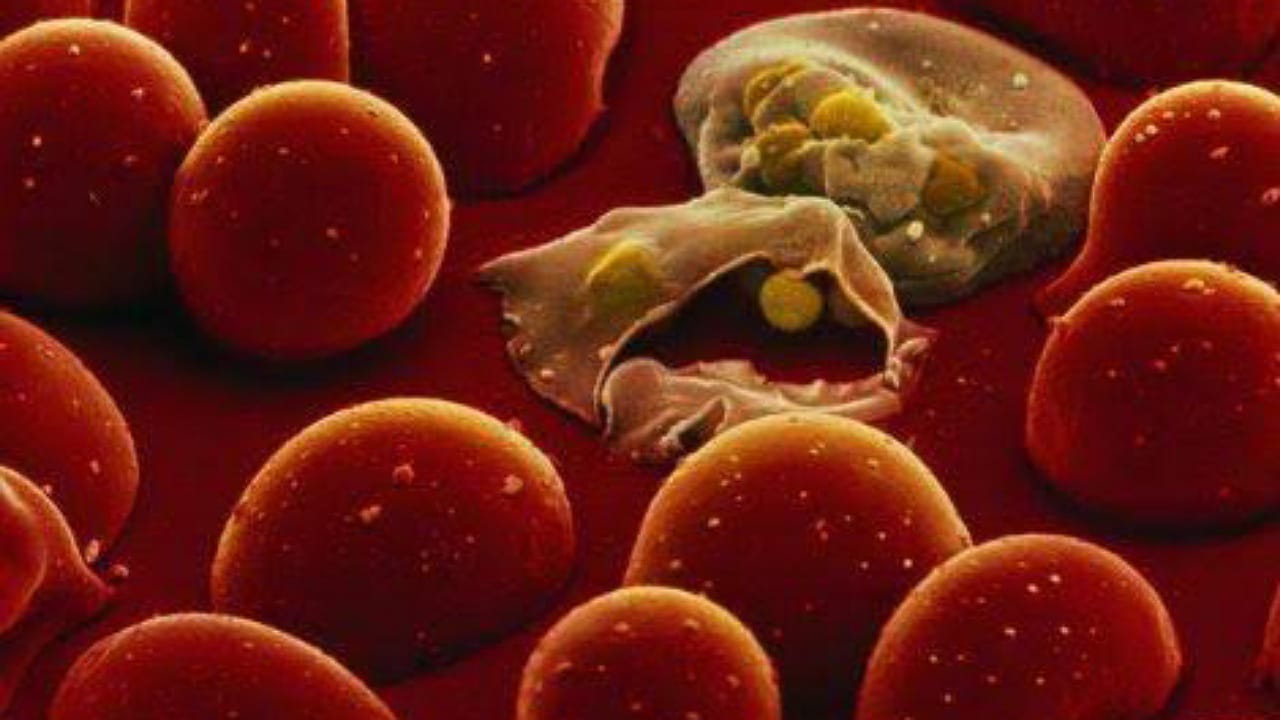

أسباب وأعراض أنيميا الفول

منذ 10 شهر

0

3079